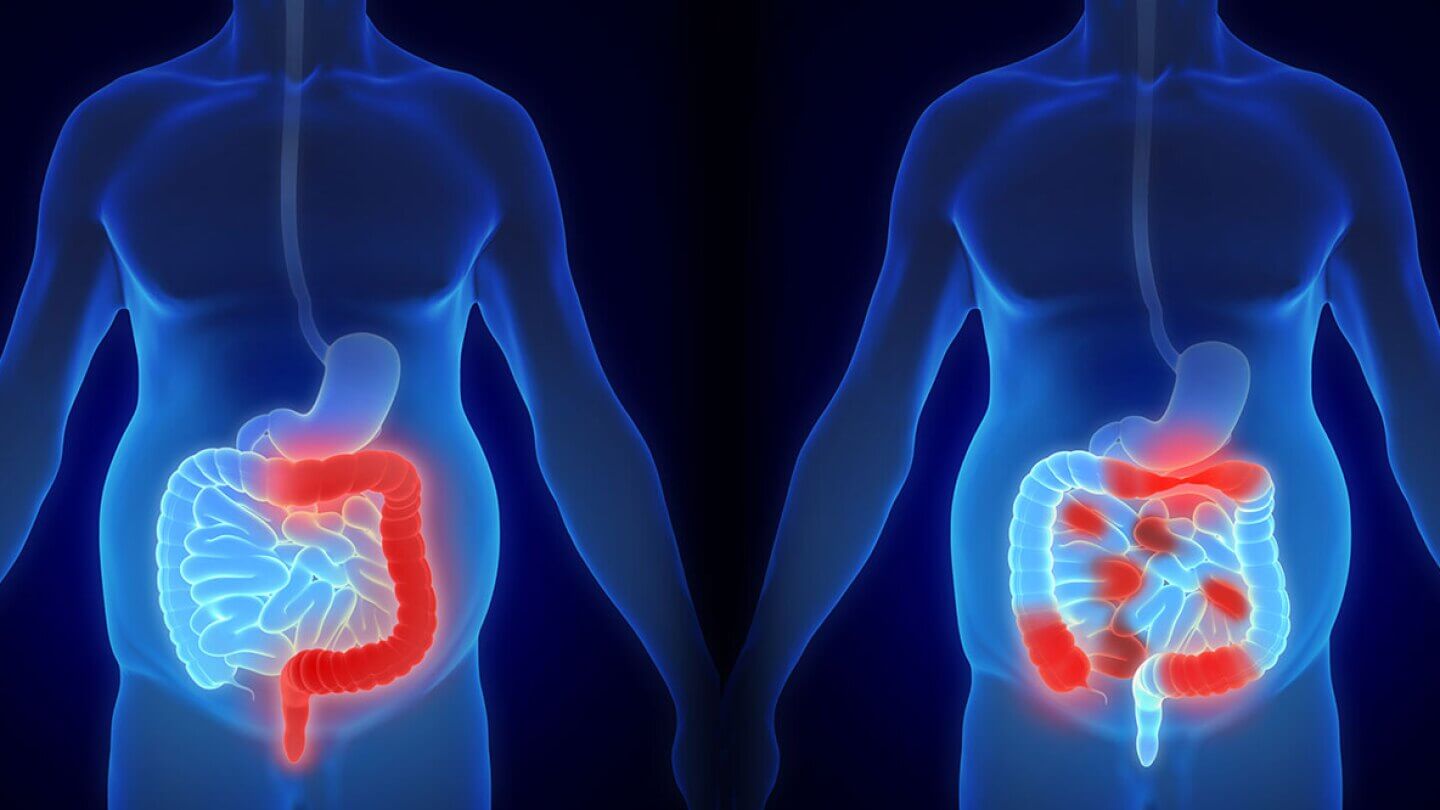

Getting told you need colon cancer surgery and then being handed a date without really understanding what that means for your body and the weeks that follow leaves most patients and families feeling considerably more scared than they need to be. Surgery removes the cancer and gives most people their best realistic shot at full recovery but knowing what colon cancer surgery actually involves, what recovery genuinely demands day after day, and what life looks like on the other side makes this whole experience far less terrifying than going through it blind. That honest preparation is exactly what this guide is designed to give you before your consultation arrives.

Colon Cancer Surgery and the Basic Goal:

The surgeon removes the section of colon where the cancer lives along with a border of healthy tissue on each side and the lymph nodes sitting nearby that could be carrying cancer cells away from the original tumor site toward other parts of the body.

Colon Cancer Surgery and Bowel Changes Afterward:

The bowel behaves noticeably differently after a section has been removed during colon cancer surgery and this adjustment period catches most patients genuinely off guard because pre-operative conversations focus heavily on the procedure itself and relatively lightly on the digestive experience that follows across the coming weeks and months of recovery at home.

More frequent bathroom trips than before, urgency that feels unfamiliar and sometimes socially difficult, changes in stool consistency, and some genuine unpredictability about when the bowel will act all show up during the adaptation period while the remaining colon gradually figures out its new configuration. This takes months for most people rather than weeks and knowing that reality before it starts prevents significant distress from assuming something has gone seriously wrong when you are actually moving through a completely expected adjustment that just takes longer than most patients are told to anticipate before their Surgery for colon cancer procedure.